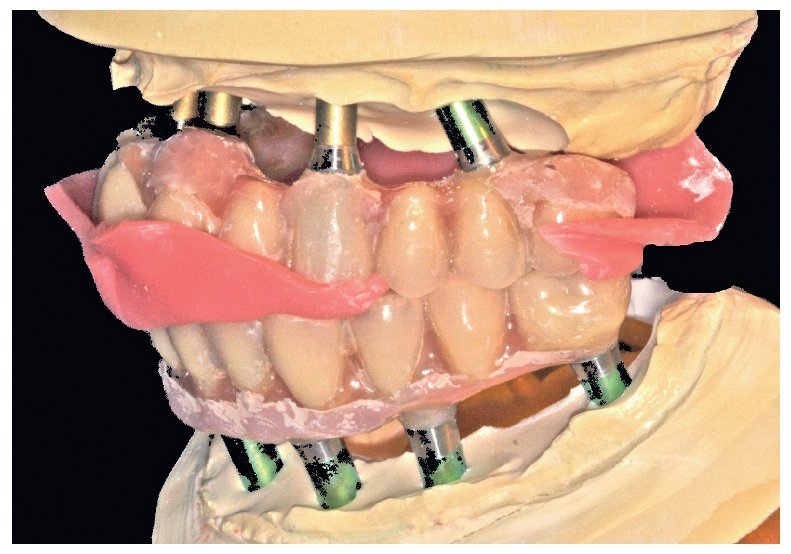

Pese a ello, es importante someter las estructuras a un control visual y mecánico, a fin de corregir eventuales discrepancias menores (figs. 99 a 102). A continuación se procede al montaje utilizando dientes protésicos prefabricados de composite (SR Phonares NHC, Ivoclar Vivadent, Ellwangen, Alemania), los cuales reproducen el tipo funcional correspondiente en virtud de sus propiedades morfológicas y estructurales y se integran armoniosamente en cuanto a su longitud dental (figs. 103 a 105). Durante la comprobación de las restauraciones protésicas, se evalúan clínica y radiológicamente ante todo la pasividad y la precisión del ajuste de la estructura. Acto seguido se lleva a cabo una comprobación de la oclusión y de la dimensión vertical, del estado de las prótesis y del tejido blando en la cresta alveolar, así como la verificación del espacio libre lingual, incluida la fonación, y el apoyo de los labios y las mejillas (figs. 106 y 107). También se debe comprobar la facilidad de higiene de la restauración de acuerdo con las habilidades manuales del paciente. A continuación se debe verificar la posición tridimensional de los dientes anteriores con los labios cerrados y durante la sonrisa, así como el aspecto global de la rehabilitación protésica.

Figs. 101 y 102. Vista lateral de las estructuras atornilladas sobre los modelos.

Figs. 103 a 105. Recubrimiento estético de las estructuras con dientes protésicos prefabricados de composite. Vista frontal y lateral a derecha e izquierda.

Durante la fase de laboratorio final pueden ser necesarios diversos ajustes estéticos y funcionales. A continuación puede confeccionarse la restauración definitiva (figs. 108 a 111). Posteriormente se procede al control final mediante sendos montajes cruzados de la restauración definitiva y del modelo de planificación (figs. 112 a 115).

Figs. 108 a 111. Vista frontal y lateral de los puentes implantosoportados terminados.